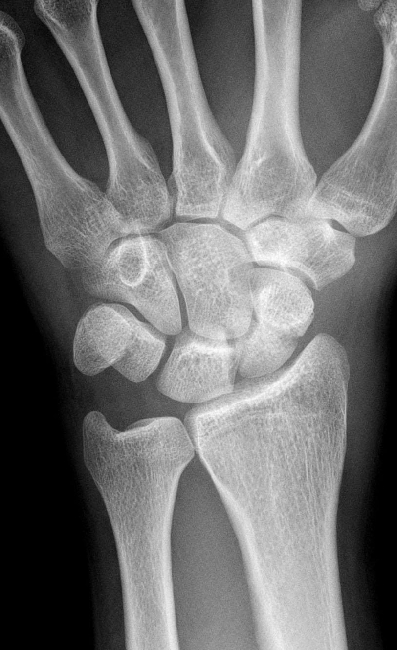

1. Bei der ersten Untersuchung handelt es sich um

- a) eine pa-Aufnahme des Handgelenkes

- b) eine Seitaufnahme des Handgelenkes

- c) eine Schrägaufnahme des Handgelenkes

- d) eine pa-Aufnahme des Vorfußes

- e) eine Seitaufnahme des Vorfußes

3. Wie ist die Reihenfolge der proximalen Handwurzelknochen von radial nach ulnar?

- a) Triquetrum >Lunatum > Pisiforme > Skaphoid

- b) Lunatum > Triquetrum > Skaphoid > Pisiforme

- c) Skaphoid > Triquetrum > Pisiforme > Lunatum

- d) Triquetrum > Skaphoid > Lunatum > Pisiforme

- e) Skaphoid > Lunatum > Triquetrum > Pisiforme

4. Wie ist die Reihenfolge der distalen Handwurzelknochen von radial nach ulnar?

- a) Hamatum > Trapezium > Trapezoideum > Capitatum

- b) Capitatum > Hamatum > Trapezium > Trapezoideum

- c) Trapezoideum > Capitatum > Hamatum > Trapezium

- d) Trapezium > Trapezoideum > Capitatum > Hamatum

- e) Trapezoideum > Trapezium > Capitatum > Hamatum

5) Was notieren sie in Ihrem Befund?

- a) Lunatum-Splitterfraktur

- b) Capitatum-Längsfraktur

- c) Skaphoid-Querfraktur

- d) Radius-Flexionsfraktur

- e) Radius-Extensionsfraktur

Warum ist es wichtig bei einer Kahnbeinfraktur zu notieren ob die Fraktur im proximalen oder distalen Drittel lokalisiert ist?

- a) Die Durchblutung des Kahnbeins erfolgt von distal, daher neigen proximale Frakturen eher zu Pseudarthrosen.

- b) Die Durchblutung des Kahnbeins erfolgt von proximal, daher neigen distale Frakturen eher zu Pseudarthrosen.